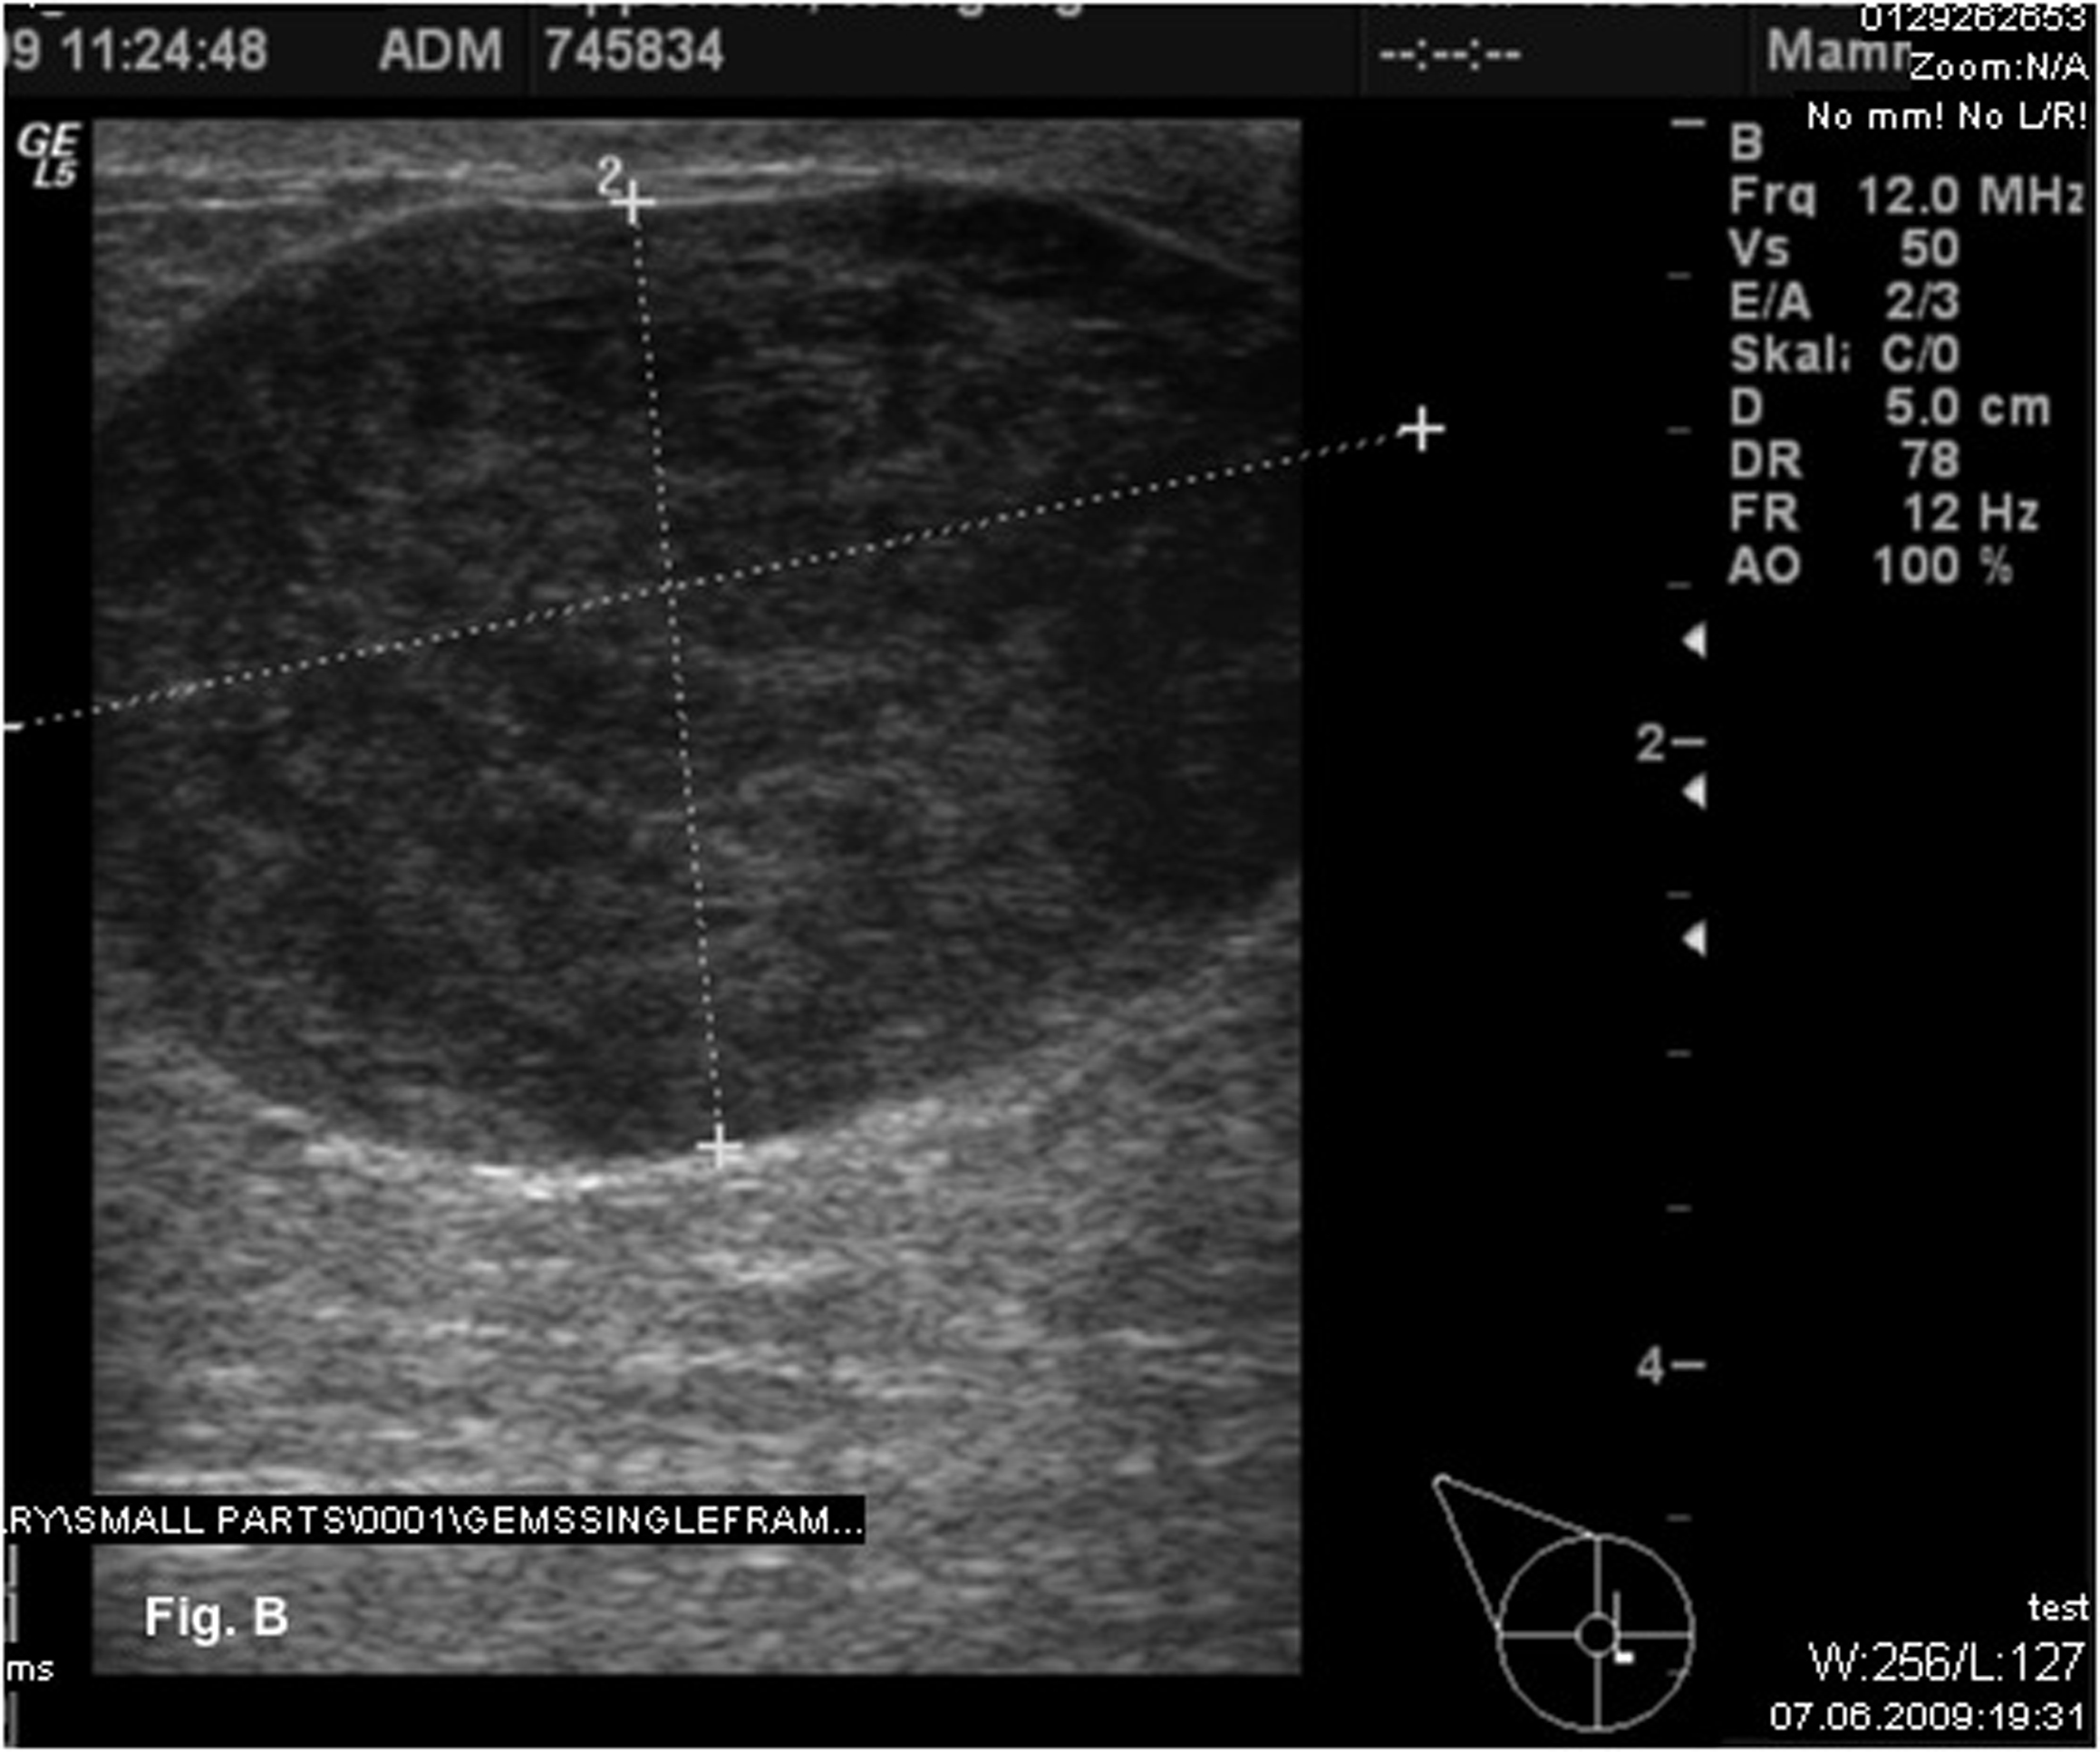

Physical examination indicated a firm palpable mass in the area of the nipple-areola complex. No suspicious cervical, supraclavicular or left axillary lymph nodes were palpable. Mammography revealed a dense, well-circumscribed solid mass of 4.6 x 3.5 cm in a central localization of the right breast (Fig. 1). The tumor was assessed as BIRADS category 3. Subsequent ultrasonography showed a hypoechoic solid echotexture that was suggestive of a fibroadenoma (Fig. 2). Preoperative core biopsy of the tumor revealed a leiomyosarcoma. Bone scintigraphy and computertomography of the chest and abdomen detected no distant metastasis.

![]() Click for large image | Figure 2. Ultrasonography showed a hypoechoic solid mass suggestive of a fibroadenoma. |